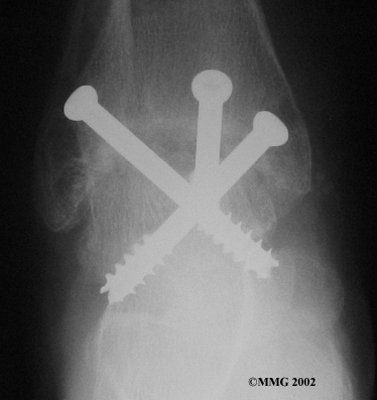

It is important when the surfaces are removed that the angles of the cut surfaces are correct. When the tibia is brought against the talus, the foot should be at a right angle to the lower leg. Once the cuts are made the bones must be held in place while they fuse. This can be done using large metal screws and metal plates if necessary. The screws are usually under the skin and are not removed unless they begin to rub and cause pain.

Inserting the screws

After ankle fusion, the physical therapists at FYZICAL West El Paso can help you learn to walk smoothly and without a limp. Although time needed for recovery varies among patients, an ankle brace will typically replace your cast after eight to 12 weeks. Your surgeon will take X-rays frequently to see if the bones are fusing together. You will probably need to use crutches during the time you wear the cast. As the fusion grows stronger, you will begin to put more weight on your foot when walking.